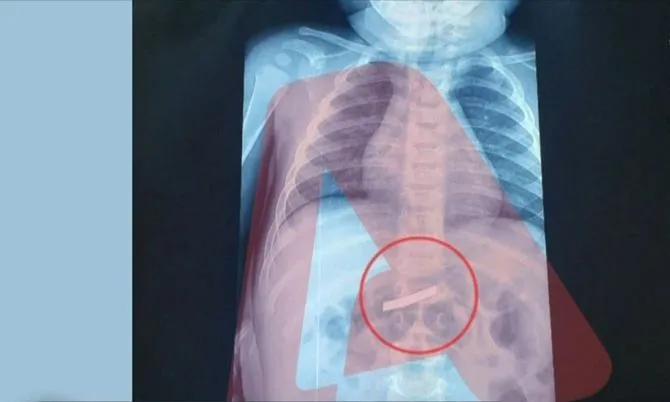

Një ngjarje e pazakontë është regjistruar në Athinë, ku një fëmijë 3-vjeçar u dërgua me urgjencë në një spital pediatrik pasi kishte gëlltitur një brisk rroje. Sipas raportimeve, menjëherë pas mbërritjes në spital, vogëlushi iu nënshtrua një grafie, e cila konfirmoi praninë e briskut në stomak. Mjekët arritën të përcaktonin me saktësi vendndodhjen e objektit, duke bërë të mundur ndërhyrjen kirurgjikale. Kirurgët realizuan operacionin për heqjen e briskut në mënyrë të sigurt dhe pa komplikacione. Fatmirësisht, ndërhyrja përfundoi me sukses dhe 3-vjeçari ndodhet në gjendje të mirë shëndetësore.